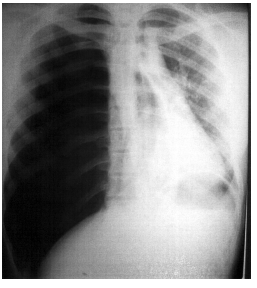

Homem de 50 anos é vitima de atropelamento. A radiografia de tórax é mostrada abaixo. Durante a avaliação clínica apresenta parada cardiorrespiratória (PCR).

Pelos dados apresentados é mais provável